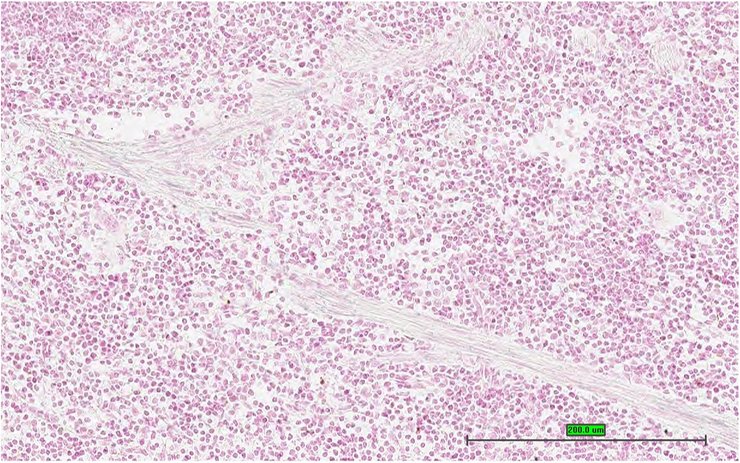

Specimen UC Davis_1862816: postnatal adult; Ctdspltm1.1(KOMP)Mbp/Ctdspl+ (more )

Structure Level Pattern Image Note

TS28: spleen Present UC Davis_1862816

Specimen UC Davis_1862817: postnatal adult; Ctdspltm1.1(KOMP)Mbp/Ctdspl+ (more )

TS28: spleen Present UC Davis_1862817

Specimen UC Davis_1862818: postnatal adult; Ctdspltm1.1(KOMP)Mbp/Ctdspl+ (more )

TS28: spleen Present UC Davis_1862818